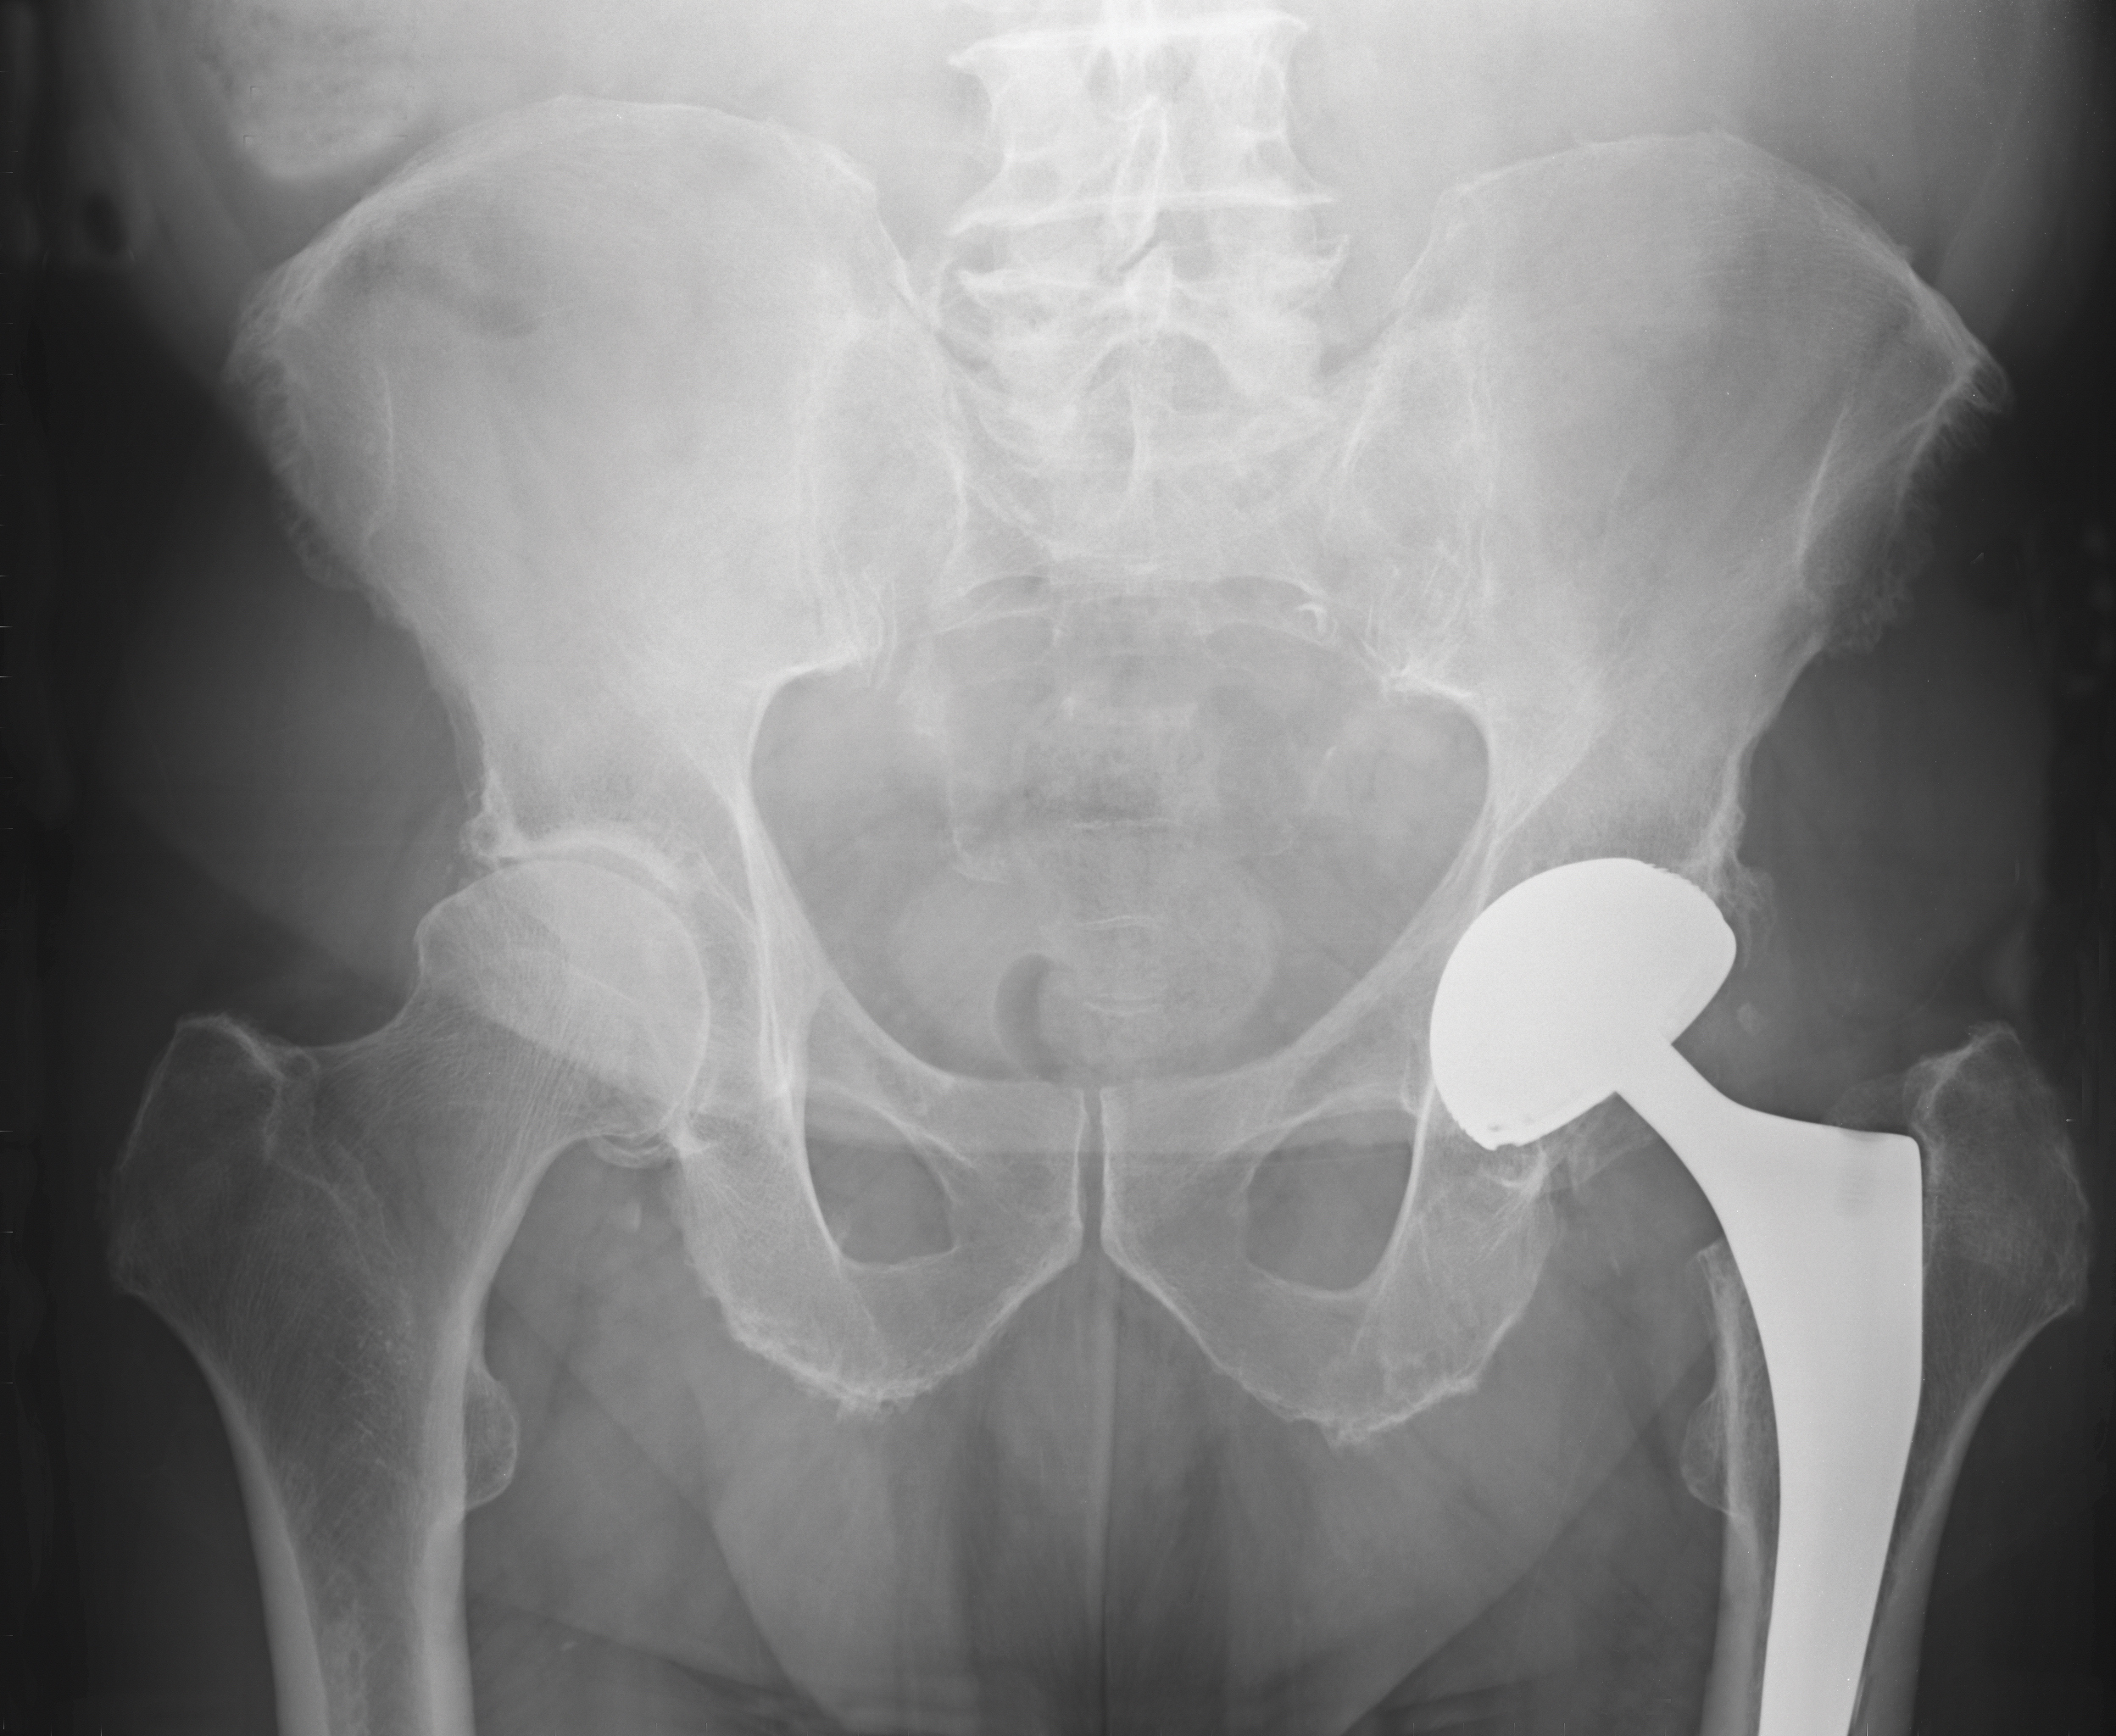

Innsetting av sementerte proteser hos eldre med underliggende sykdommer og lårhalsbrudd har gitt flere uønskede effekter. På tide å justere praksis?

Plastmaterialet polymetylmetakrylat ble tatt i bruk for nesten hundre år siden innen tannmedisinen. I mellomkrigstiden ble materialet formet til proteser og satt inn i ødelagte hofteledd. Disse implantatene smuldret opp og ble forsøkt erstattet av metallproteser. Disse destruerte benet og løsnet (1, 2).

Metallproteser var ingen suksess inntil en engelsk kirurg, sir John Charnley, i perioden 1950–60 utviklet en teknikk der akrylsement ble sprøytet ned i benmargen før den polymeriserte og derved støpte fast protesen. Pasienten kunne da bevege seg uten smerter (3). Dette ble en stor suksess og starten på en ny æra for behandling av sykdom og skade i hofteleddet.

Innsetting av usementerte proteser er ikke assosiert med de samme alvorlige perioperative komplikasjonene som sementerte implantater (6–8). Imidlertid har innsetting av usementerte proteser vært assosiert med periprotetiske frakturer, tidlig løsning og reoperasjoner (9). Norsk hoftefrakturregister har derfor valgt å anbefale bruk av sementerte proteser til alle pasienter med lårhalsbrudd over 70 år (10, 11). Tilsvarende konsensusanbefaling kommer fra NICE i England (12).

Vi har nå mange generasjoner med akkumulert vitenskapelig og klinisk kunnskap om de underliggende kjemiske og cellulære prosessene som kan lede til intraoperativ instabilitet og død ved innsetting av sementerte proteser. Det er derfor vanskelig å rettferdiggjøre innsetting av sementerte proteser til alle eldre pasienter.